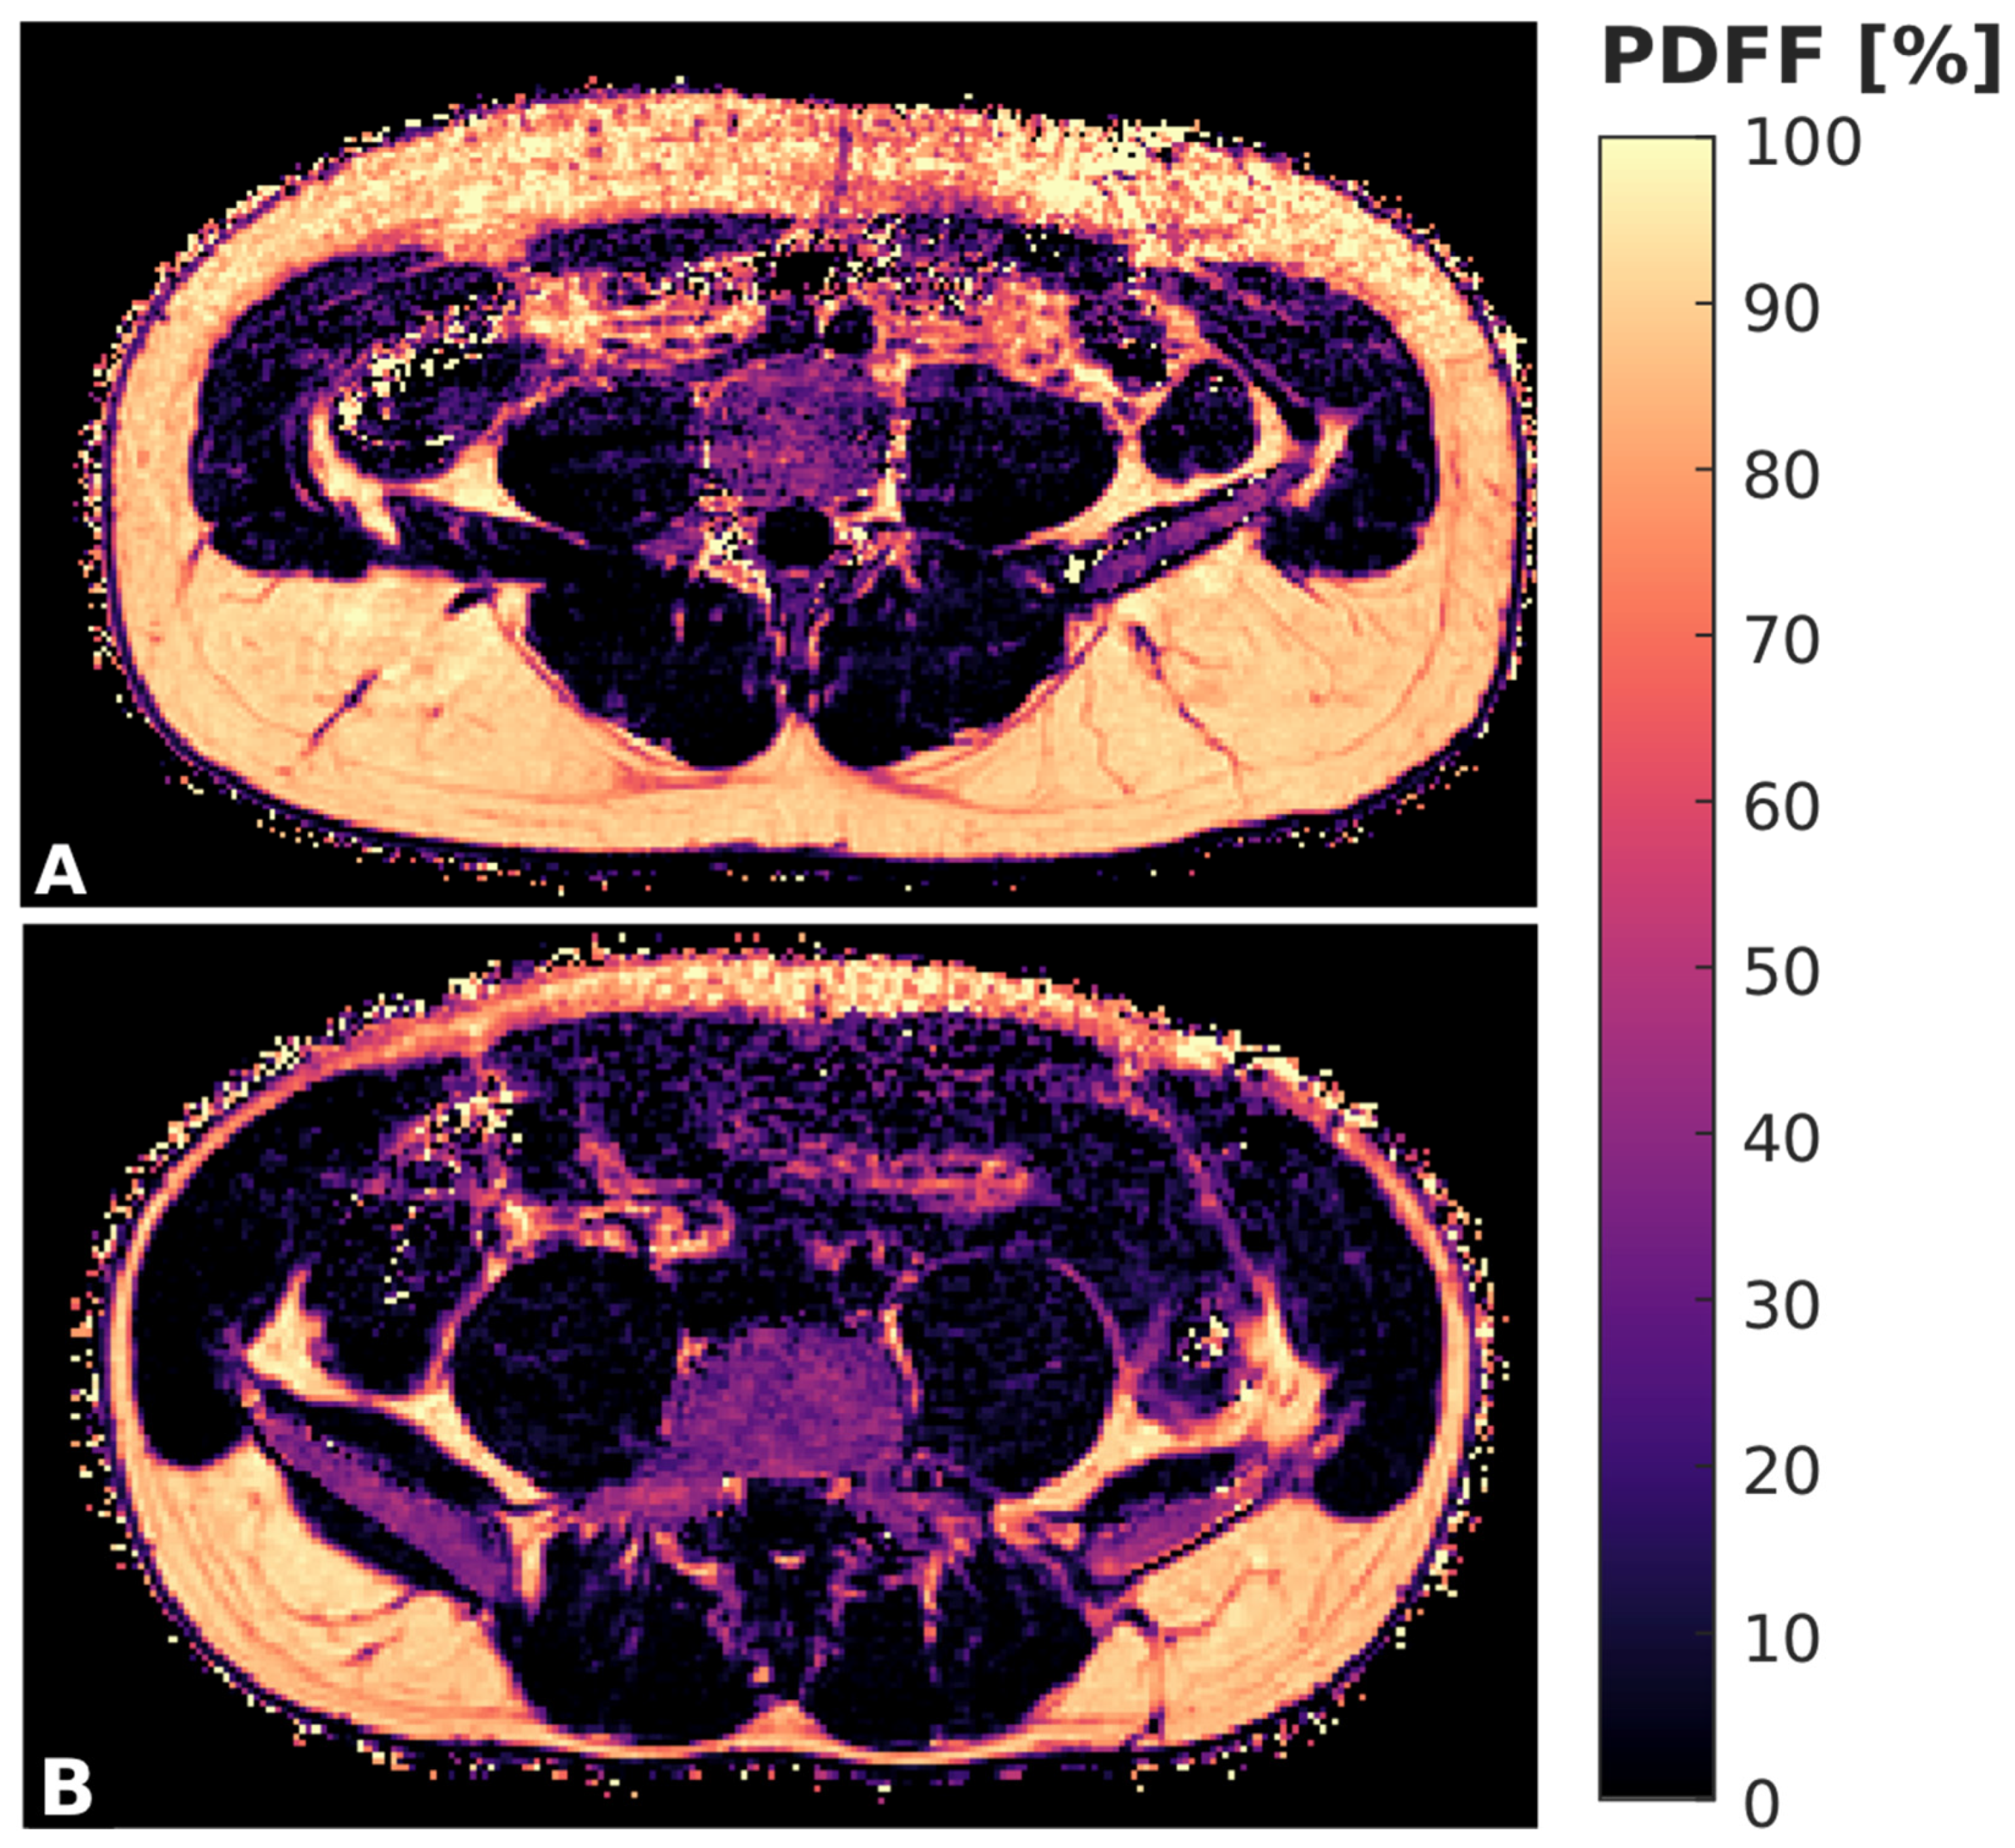

The gradient echo imaging data were processed online using the fat quantification routine of the MRI vendor. The routine procedure first performed a phase error correction and then a complex-based water–fat decomposition using a pre-calibrated seven-peak fat spectrum and a single T2* to model the signal variation with TE. The imaging-based PDFF map was computed as the ratio of the fat signal over the sum of fat and water signals (Figure 1).

Figure 1.

Color-coded, axially acquired PDFF maps derived from CSE-MRI of a 33 year old male (A) and 27 year old female (B) subject.